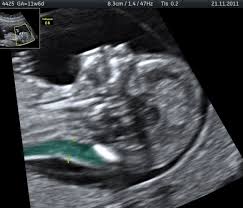

12 Week Ultrasound Maternal Fetal Medicine

12 Week Pregnancy Dating Scan What Will It Tell Me Madeformums

Down syndrome is a genetic disorder caused when abnormal cell division results in an extra full or partial copy of chromosome 21. This test is done between 15 and 20 weeks of pregnancy. In 2011 a nicely done experiment by Marshall et al showed that regular hamstring stretching substantially increased range of motion in normal university kids95 Specifically after a 4-week stretching program consisting of 4 hamstring and hip stretches performed 5 times per week their range increased about 16 or 20. Down syndrome is a genetic disorder caused when abnormal cell division results in an extra full or partial copy of chromosome 21. In Down syndrome the nuchal translucency measurement is abnormally large as shown on the left in the ultrasound image of an 11-week fetus. How is a dating scan performed. The 20-Week Anatomy Scan May 2017.